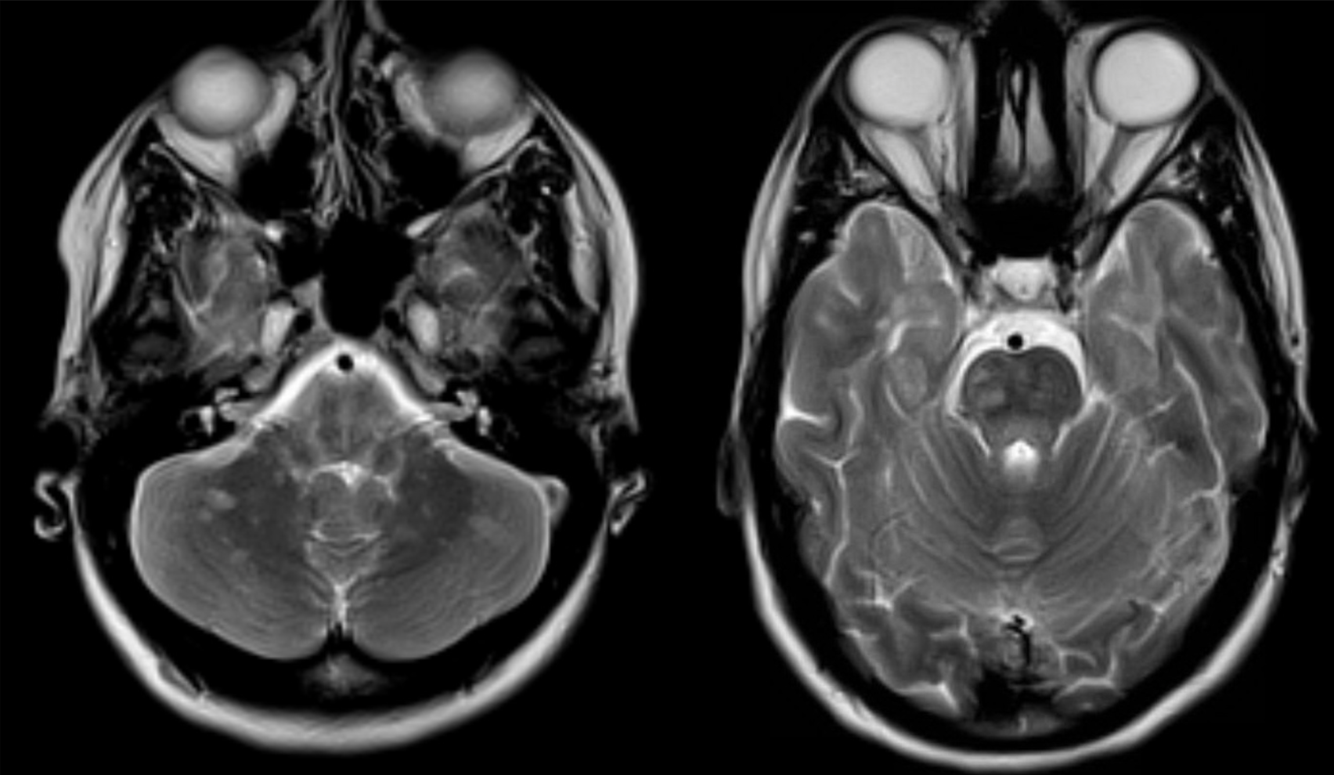

A 30 year-old female presented with with double vision.

Multiple sclerosis - infratentorial lesions